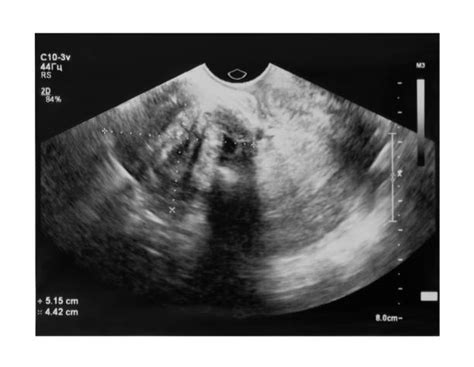

Výskyt heterotopickej gravidity v rámci asistovanej reprodukcie kolíše medzi 0,75 % a 2,9 %. Pri liečbe klomiféncitrátom sa incidencia heterotopickej gravidity zvyšuje na 1/900 tehotenstiev. V prípade kombinácie intrauterinnej a extrauterinnej gravidity je včasná diagnostika mimodaterinného tehotenstva pri absencii klinických príznakov takmer nemožná. Väčšina kazuistík referuje prípady heterotopickej gravidity diagnostikované až v štádiu ruptúry tubárnej gravidity, hemoperitonea a hemoragického šoku.

V prípade kombinácie intrauterinnej a extrauterinnej gravidity je včasná diagnostika mimodaterinného tehotenstva pri absencii klinických príznakov takmer nemožná. V takom prípade je indikovaná urgentná operačná intervencia a liečba hemoragického šoku. Sanácia ektopickej tubárnej gravidity pri perzistujúcom vitálnom intrauterinnom tehotenstve sa dá riešiť aj konzervatívne. V úvahu prichádza aplikácia prostaglandínov alebo hyperosmolárnej glukózy do vajcovodu s molou, a to buď laparoskopicky alebo transvaginálne pod ultrazvukovou kontrolou.

Pri podozrení na heterotopické tehotenstvo je vhodné sledovať pacientku za hospitalizácie s pravidelnými ultrazvukovými kontrolami a monitorovaním dynamiky sérových hladín hCG.